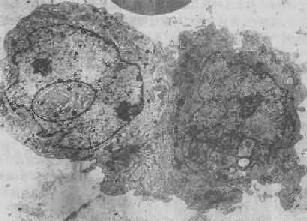

图1-3 核内假包含体

垂体嗜酸性细胞瘤的瘤细胞,左侧瘤细胞核内可见一卵圆形包含体,有膜包绕,内含细胞器和胞浆分泌颗粒×8400